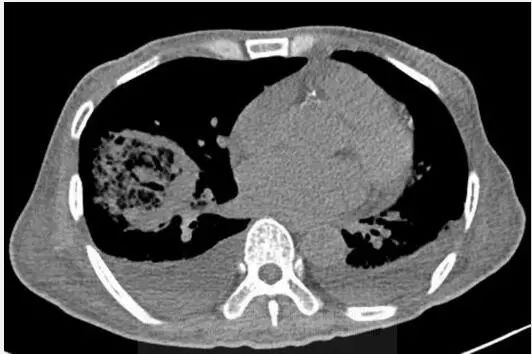

图1胸片示右肺下叶空洞性实变和左肺下叶实变。CT示右肺下叶类圆形实变伴中央磨玻璃影(反晕征),和空洞性病变。可见双侧胸腔积液。